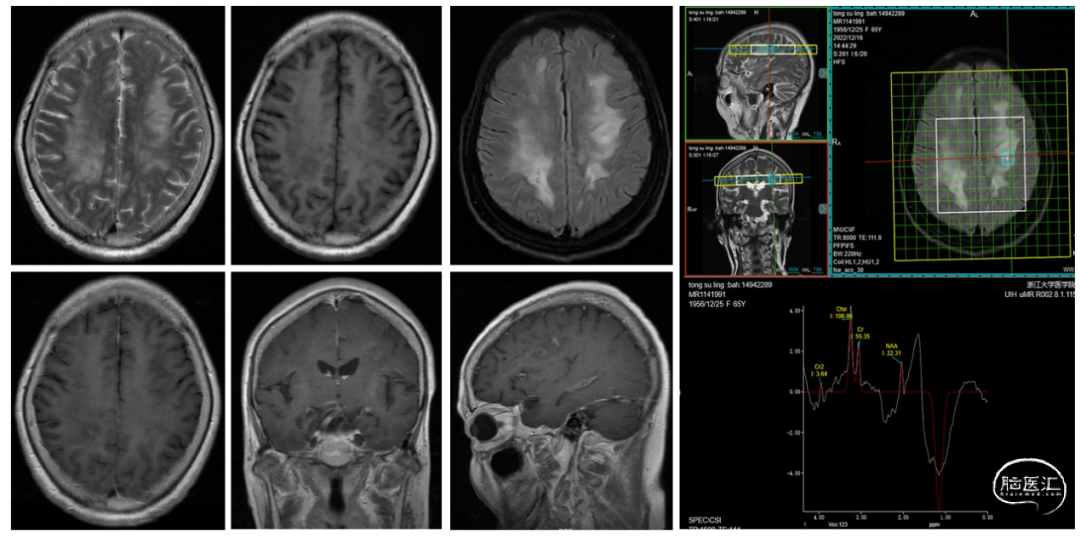

入院后进一步完善磁共振波谱(MRS)检查,提示:NAA明显下降,Cho轻度升高,Cho/NAA=2.20,Cho/Cr=1.68,MRS提示非肿瘤性病变(图1)。脑脊液NGS检测:脱髓鞘抗体阴性、EB病毒、副肿瘤及自免脑检测阴性。

IVLBCL的影像学表现缺乏特异性,头颅MRI是最常用的检查方法。典型的MRI表现为脑内多发散在的病灶,可累及大脑半球、小脑、脑干等部位,T1WI呈等或稍低信号,T2WI及FLAIR呈高信号,弥散加权成像(DWI)呈高信号,提示病变区细胞密度增高,水分子弥散受限。增强扫描多表现为轻度斑片状、结节状或环形强化,强化程度一般较轻。部分患者可出现脑膜强化。MRS检查对IVLBCL的诊断有一定的辅助价值,通常表现为Cho/Cr比值升高,NAA/Cr比值降低,与其他脑肿瘤相似,但一般无明显的Lip峰[2,3]。本例患者头颅MRI表现为右侧小脑半球、双侧脑室旁及半卵圆区多发弥散受限信号,增强可见局部轻度斑片状强化,MRS提示非肿瘤性病变,影像学表现不典型,易误诊为其他脑部疾病,如脑梗死、脱髓鞘疾病等。